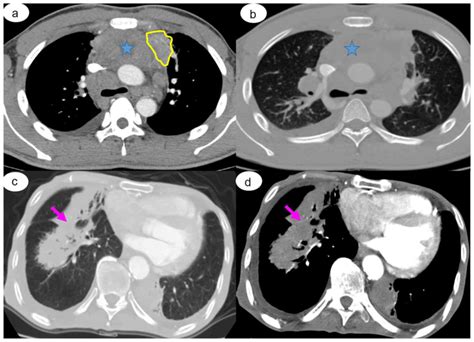

• Watchful Waiting: This is the most common approach for small, low-risk nodules. The patient will undergo a "follow-up" CT scan at specific intervals (often 3, 6, or 12 months) to see if the nodule has changed in size or shape.

• Comparison with Old Scans: If previous imaging is available, radiologists will compare the new scan to older ones. If the nodule has remained stable for two or more years, it is almost certainly benign.

• PET Scans or Biopsies: If a nodule appears suspicious or grows during the observation period, the physician may order a PET scan to check for metabolic activity or a biopsy to extract a small sample of tissue for laboratory testing.